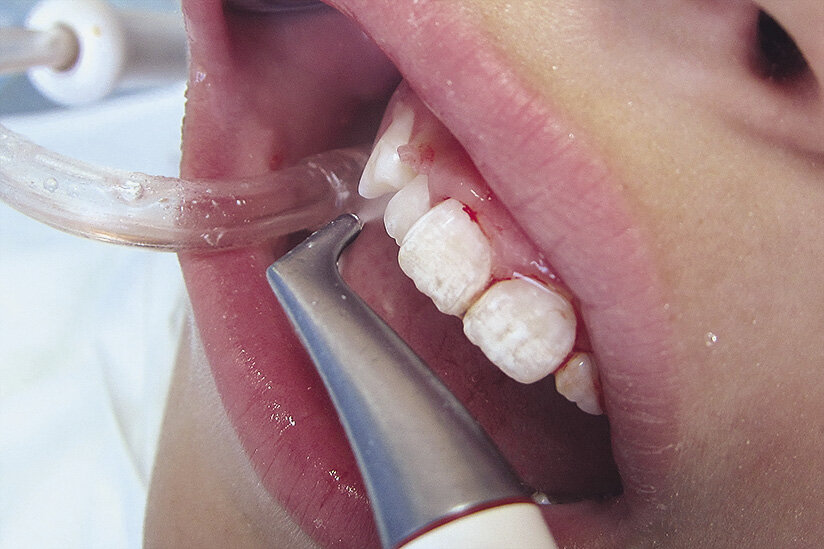

Причин кровоточивости десны во время и после чистки зубов достаточно много. Если кровь появляется не часто, то вполне вероятно, что её появление вызвано травматизацией слизистых оболочек. В основном это происходит при использовании щёток со слишком жёсткой щетиной. Травмировать ткани можно и зубочисткой, а также острыми предметами, не предназначенными для совершения манипуляций в ротовой полости. При регулярной и усиливающейся кровоточивости дёсен необходимо исключить:

Причин кровоточивости десны во время и после чистки зубов достаточно много. Если кровь появляется не часто, то вполне вероятно, что её появление вызвано травматизацией слизистых оболочек. В основном это происходит при использовании щёток со слишком жёсткой щетиной. Травмировать ткани можно и зубочисткой, а также острыми предметами, не предназначенными для совершения манипуляций в ротовой полости.